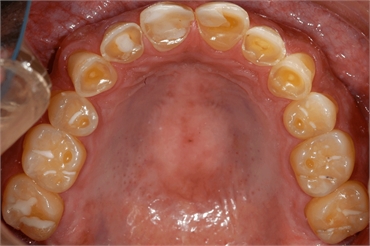

While outside manifestations are subtle, bulimia nervosa has more obvious oro-facial

manifestations. The first is perimylolysis, or the smooth erosion of dental enamel on lingual

surfaces of the teeth. This is caused by exposure to gastric acid in people with chronic vomiting.

Initially, erosion appears as a glassy surface on the palatal surfaces of maxillary anterior teeth.

It can be observable after a patient has been binging and purging for anywhere from two

months to two years. The patient may also complain of thermal sensitivity. The extent of erosion

depends on diet, the frequency of binging and purging, and his or her oral hygiene habits. If left

to progress erosion can expose dentin and cause teeth to appear yellow or grey.